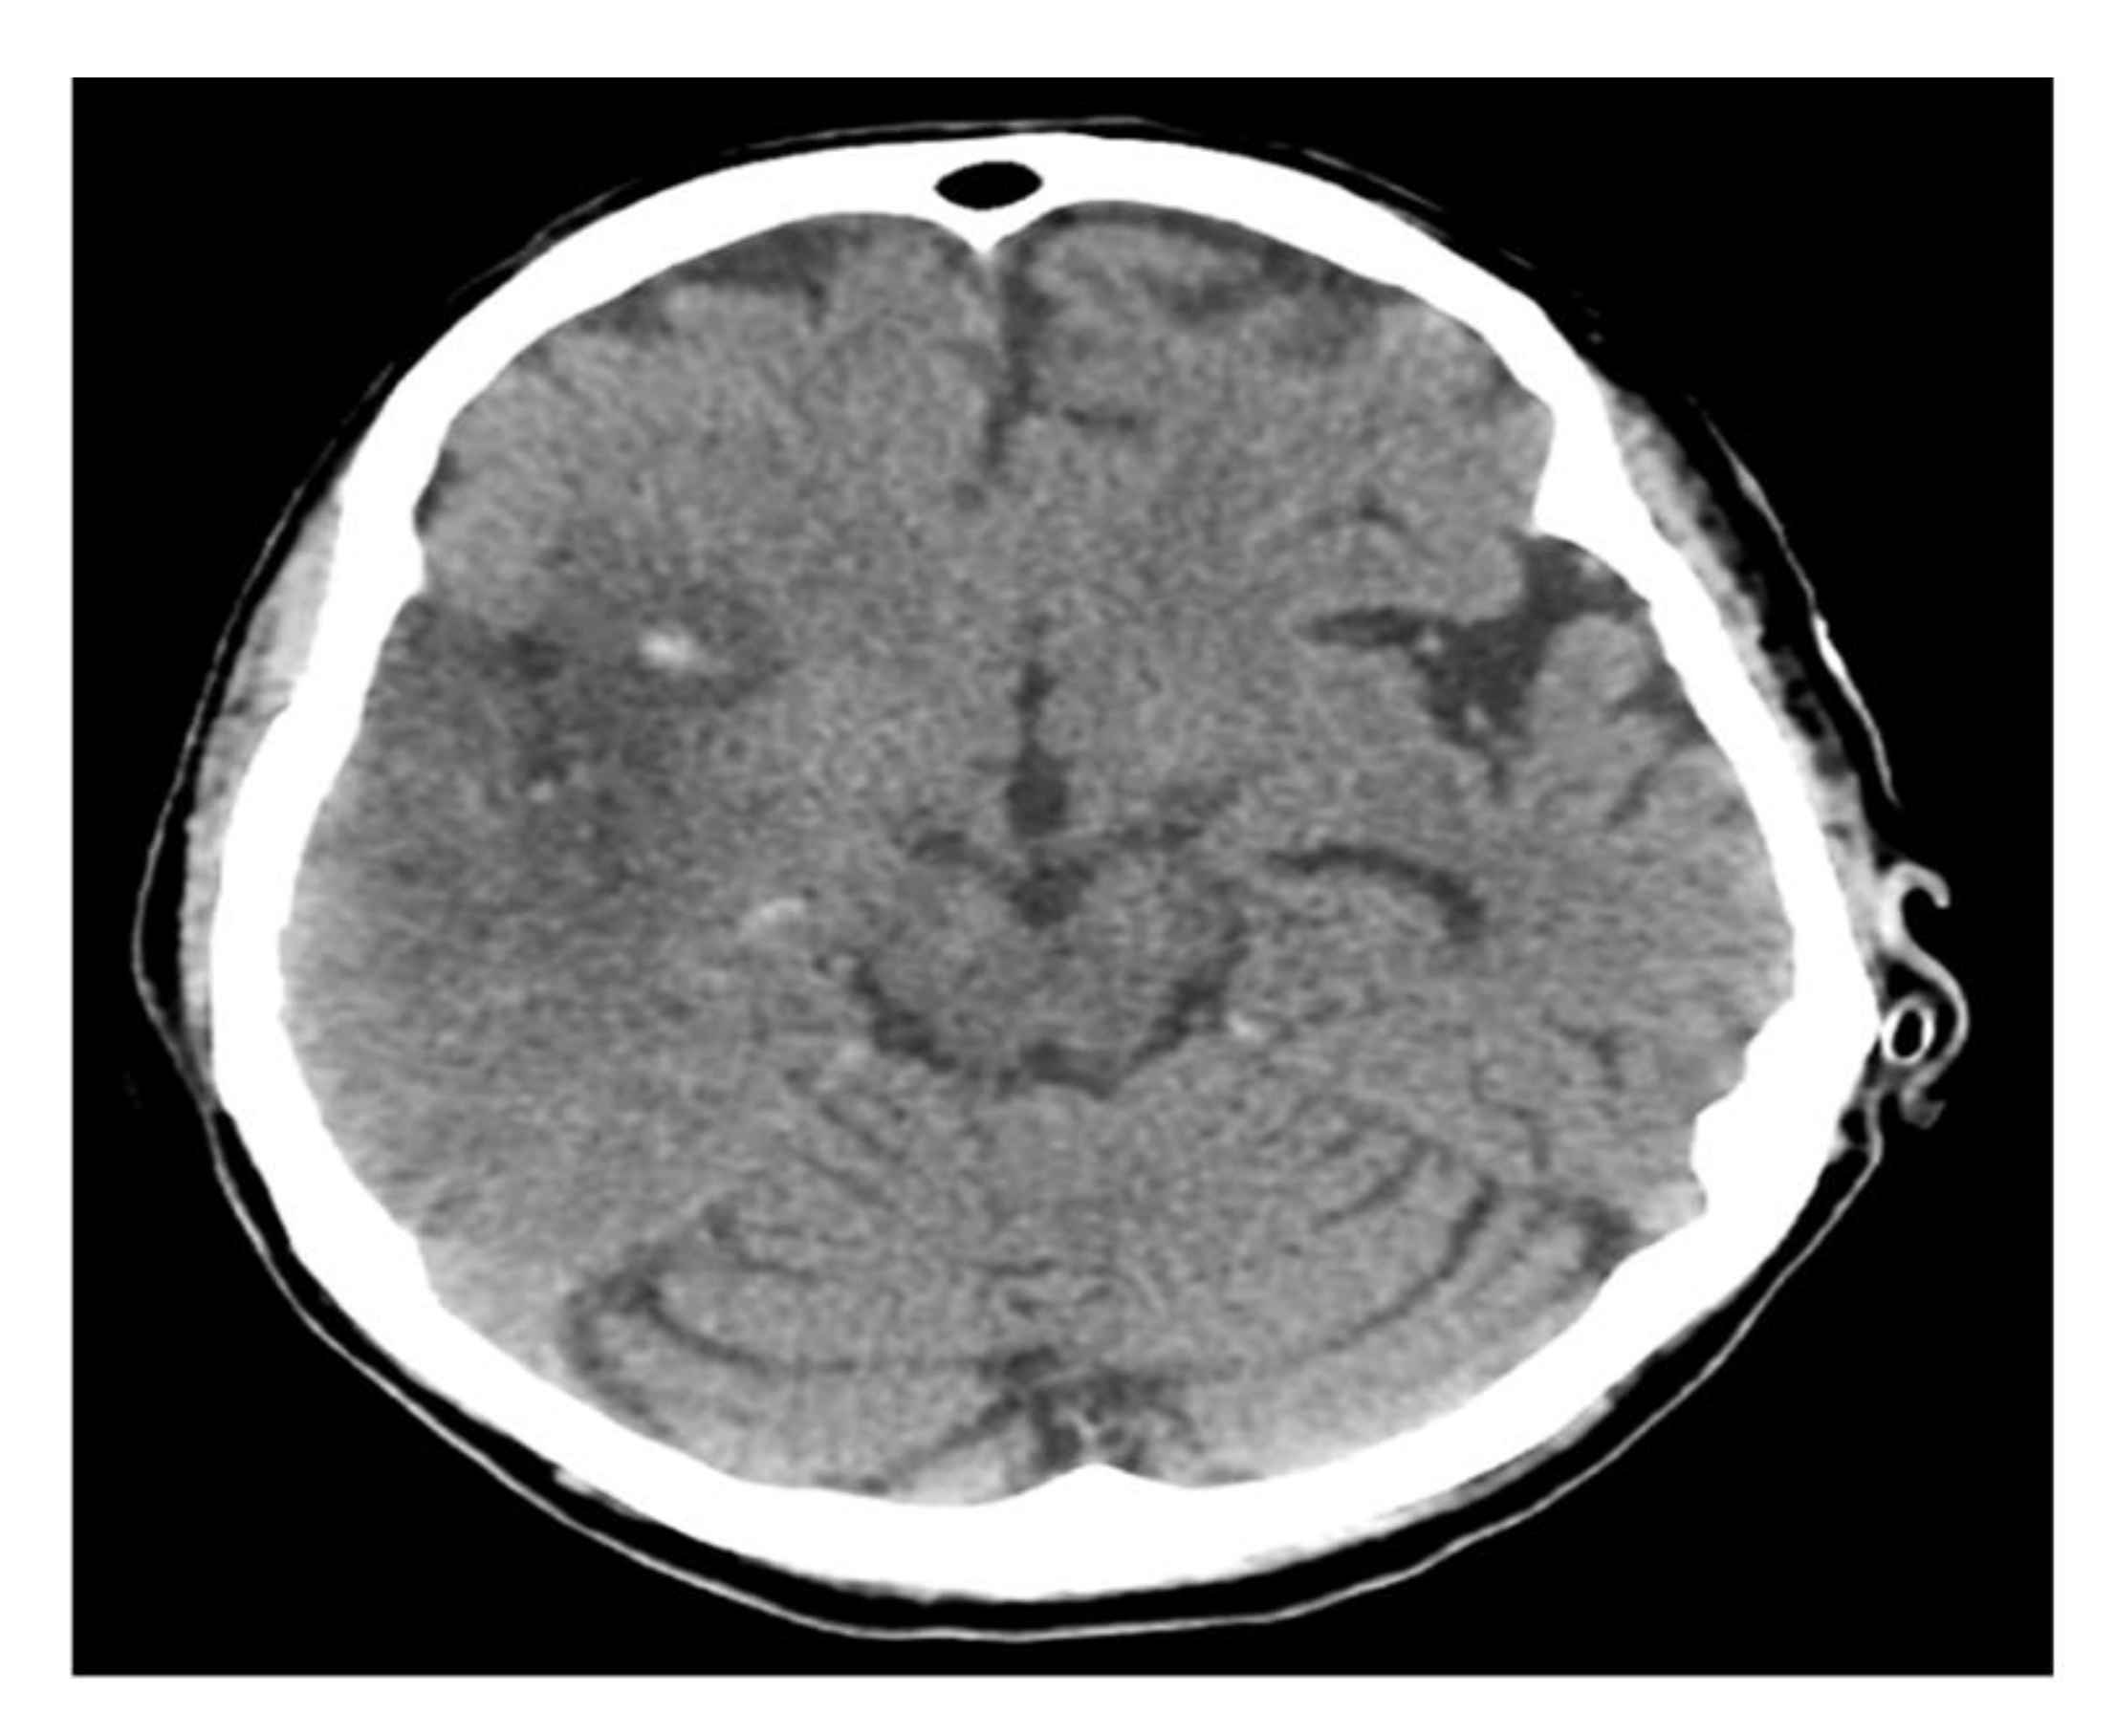

A computerized brain tomography (CT) and CT arteriogram (CTA) showed acute right middle cerebral artery (MCA) ischemic infarction with complete occlusion of the suitable M1 and a partial filling defect in the distal M2 segment. She underwent endovascular thrombectomy with partial recanalization and was kept in an intensive care unit (ICU) for close monitoring. A follow-up CT brain showed interval development of hemorrhagic transformation (Figure 1).

Figure 1.

Brain CT scan.